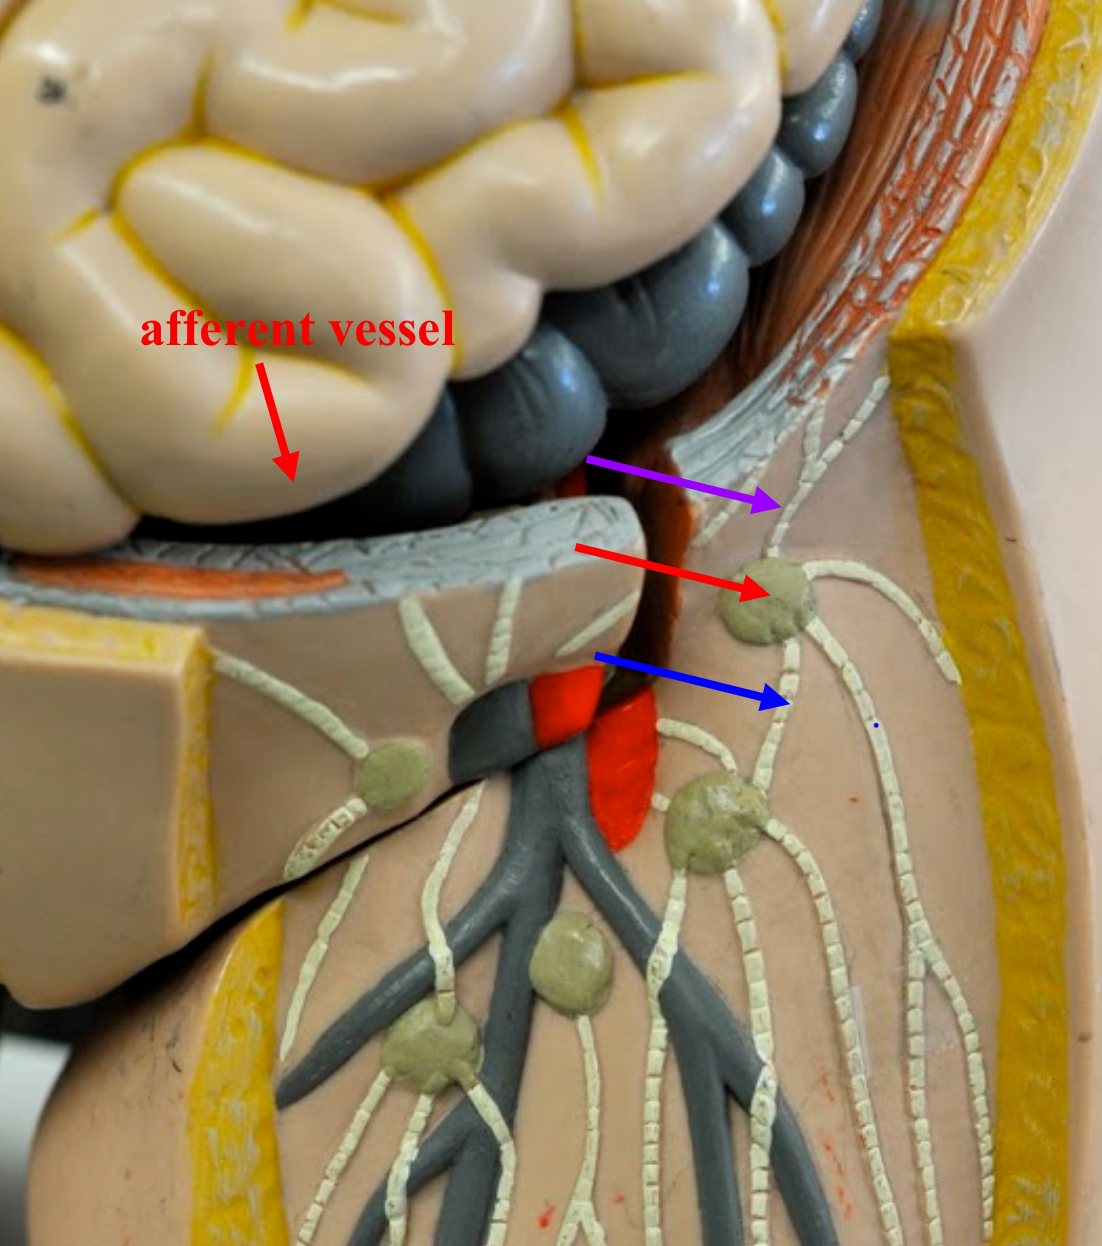

afferent lymphatic vessels (lymph node)

Entrance on the lymph node for lymphatic vessels to bring lymph fluid

hilum (lymph node)

An indentation where blood vessels and nerves reach the lymph node.

efferent lymphatic vessels (lymph node)

the vessels leaving the concave hilum of the lymph node carry lymph away and onward to the venous system.

Are there more afferent or efferent lymphatic vessels?

Afferent lymphatic vessels generally outnumber efferent lymphatic vessels.

lymphatic capsule (lymph node)

The connective tissue that surrounds and protects the lymph node.

trabeculae (lymph node)

the extends inward and partition the interior of the node.